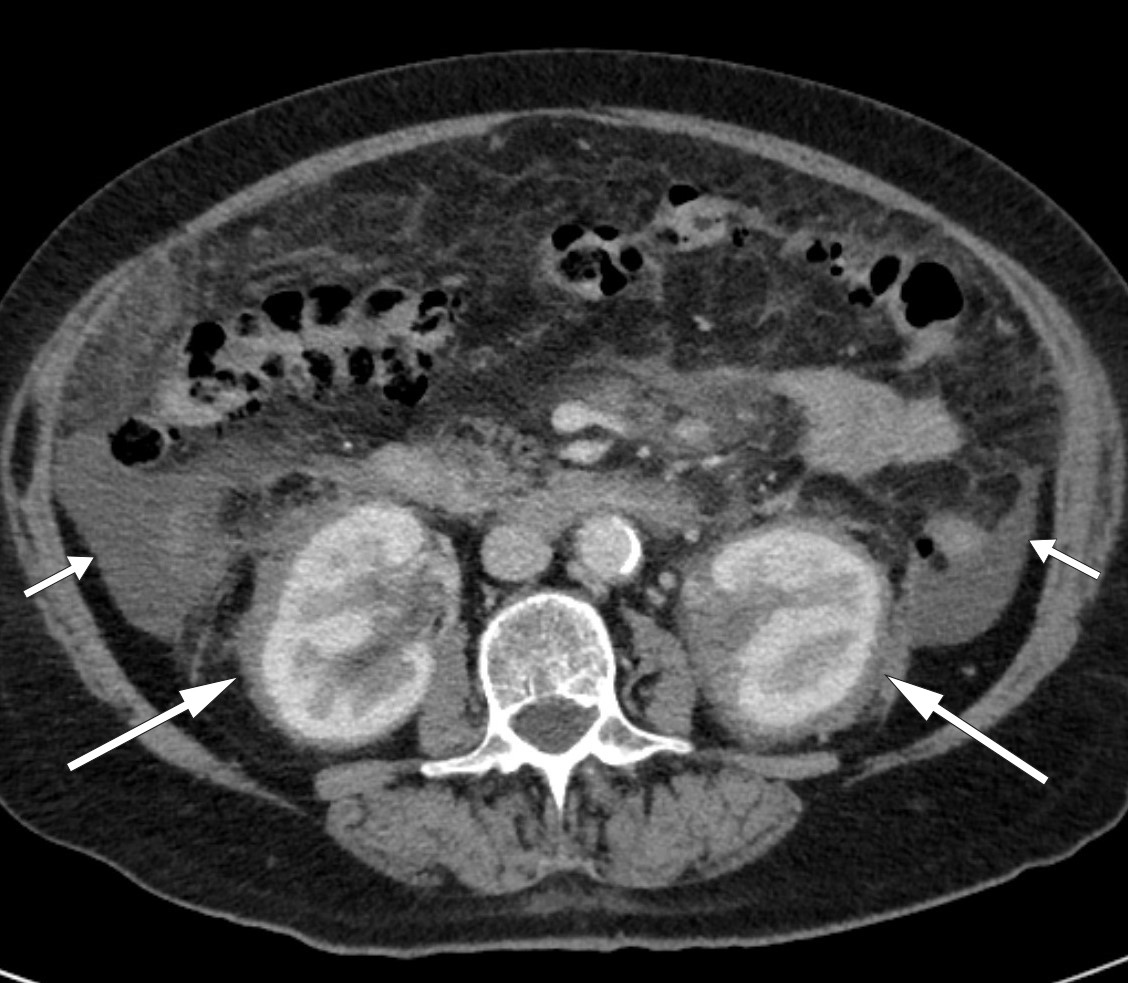

I tillegg til de perinefriske forandringene var det påfallende funn på CT thorax (fig 2) og helkroppsscintigrafi (fig 3). Som et bifunn ble det også funnet en liten lungeembolus. MR hjerte og ekkokardiografi påviste lokalt fortykket perikard, mens MR caput og orbita viste normale funn. Abdominal paracentese viste CD68-positive og CD1a-negative makrofager og ingen tegn til mikrober. I ascitesvæsken, som var gjennomskinnelig og gul, var albuminnivået 13 g/l og proteinkonsentrasjonen 24 g/l (under 30 g/l tydet på transudat). Serum-ascites-albumin-gradienten (SAAG) var 9 g/l, forenlig med at årsaken til ascites ikke var portal hypertensjon. Leukocytter i ascitesvæsken var 0,20 · 109/l, noe som utelukket spontan bakteriell peritonitt. På blodutstryk var det granulocytose og trombocytose, mens benmargsutstryk viste reaktiv/normal benmarg. Benmargsbiopsi viste noen svakt reaktive megakaryocytter, og biopsier fra femur påviste kun osteomyelosklerose. Biopsi fra perinefrisk vev viste fibrose og histiocytter som var positive for CD68 og negative for CD1a, samt en uspesifikk reaksjon for S100-proteiner. Genetisk testing for BRAF-mutasjon var negativ.

Symmetrisk osteosklerose i diafysene og metafysene i lange rørknokler, inflammatoriske forandringer rundt aorta (coated aorta) og perirenal infiltrasjon av histiocytter (hårete nyrer) er typiske radiologiske funn (25, 28, 29). Sistnevnte er nærmest patognomonisk for tilstanden og en viktig grunn til at diagnosen tidlig ble mistenkt hos vår pasient. Det histologiske bildet er karakterisert av lipidfylte såkalte skumhistiocytter, ofte kombinert med fibrose. Immunhistokjemisk vil de være positive for CD68, CD163 og faktor XIIIa, og i noen tilfeller for S100, som skiller dem fra histiocytter ved en del andre tilstander. De vil også være negative for CD1a og langerin (CD207) (27).